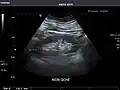

Abdominal Ultrasound (Full Exam)

STRUCTURED REPORT

(Technique: Transabdominal ultrasonography; Device: Toshiba Aplio XG)

Liver: Diffusely homogeneous and normal in echogenicity. No focal mass or contour nodularity. No intrahepatic biliary ductal dilatation.

Portal Vein: Patent main portal vein.

Gallbladder: No stones, wall thickening, or pericholecystic fluid.

Common Bile Duct: Nondilated measuring 1.3 mm at the level of the porta hepatis.

Pancreas: Visualized portions unremarkable.

Spleen: Normal in size.

Kidneys: Right and left kidneys measure 11.5 cm and 12 cm in length respectively. No hydronephrosis. Small left lower pole kidney cyst.

Ascites: None.

Aorta: Visualized portions normal in caliber, 16 x 15 mm.

IVC: Normal.

IMPRESSION:

Normal abdominal ultrasound.